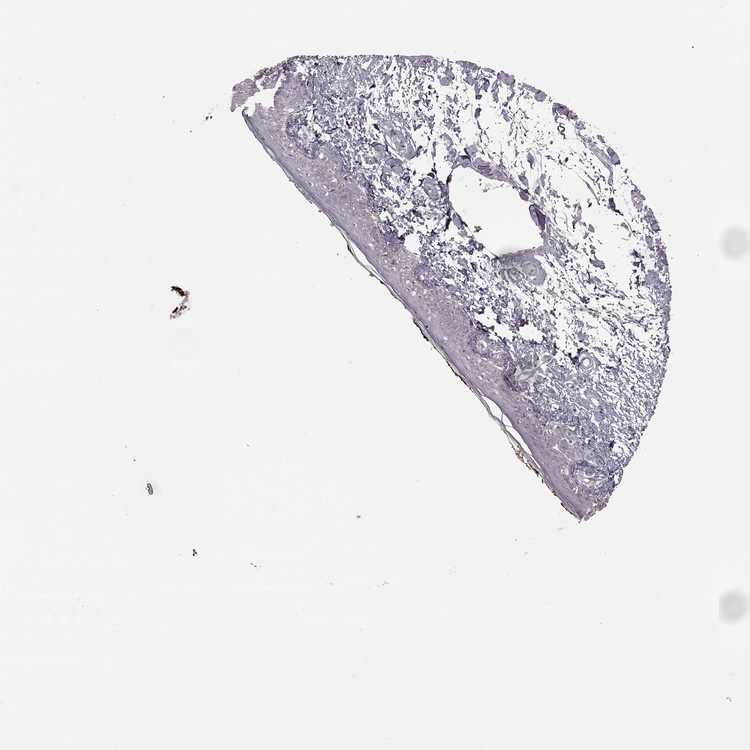

SKIN 1 - Antibody stainingi

Antibody staining in the annotated cell types in the current human tissue is reported as not detected, low, medium, or high, based on conventional immunohistochemistry profiling in selected tissues. This score is based on the combination of the staining intensity and fraction of stained cells.

Each image is clickable and will lead to virtual microscopy that enables deeper exploration of all samples and also displays staining intensity scores, fraction scores and subcellular localization as well as patient and tissue information for each sample.

Antibody HPA035981Antibody CAB038418Antibody CAB076386

Langerhans Not detectedNot detectedNot detected

Fibroblasts Not detectedNot detectedNot detected

Keratinocytes Not detectedNot detectedNot detected

Melanocytes Not detectedNot detectedNot detected